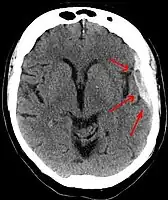

-

Acute-on-chronic subdural hematoma -

Acute traumatic subdural hematoma -

Acute on chronic subdural hematoma -

A subdural hematoma demonstrated by CT

Subdural hematomas occur most often around the tops and sides of the frontal and parietal lobes.[9][10] They also occur in the posterior cranial fossa, and near the falx cerebri and tentorium cerebelli.[9] Unlike epidural hematomas, which cannot expand past the sutures of the skull, subdural hematomas can expand along the inside of the skull, creating a concave shape that follows the curve of the brain, stopping only at dural reflections like the tentorium cerebelli and falx cerebri.

On a CT scan, subdural hematomas are classically crescent-shaped, with a concave surface away from the skull. However, they can have a convex appearance, especially in the early stages of bleeding. This may cause difficulty in distinguishing between subdural and epidural hemorrhages. A more reliable indicator of subdural hemorrhage is its involvement of a larger portion of the cerebral hemisphere. Subdural blood can also be seen as a layering density along the tentorium cerebelli. This can be a chronic, stable process, since the feeding system is low-pressure. In such cases, subtle signs of bleeding—such as effacement of sulci or medial displacement of the junction between gray matter and white matter—may be apparent.